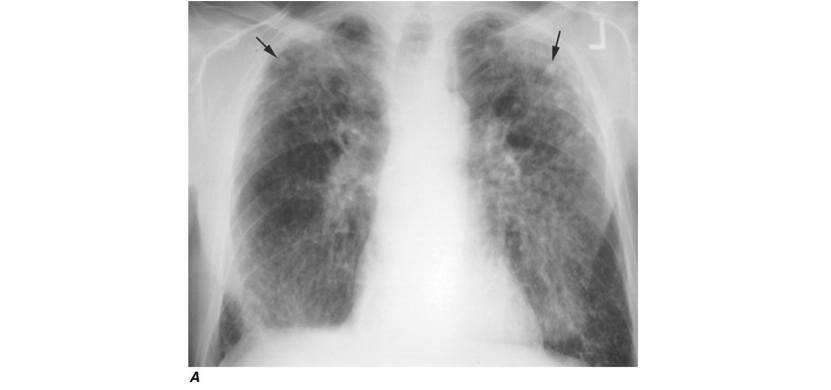

The chest radiograph can be used to detect the pulmonary manifestations of asbestos exposure. Past exposure is specifically indicated by pleural plaques, which are characterized by either thickening or calcification along the parietal pleura, particularly along the lower lung fields, the diaphragm, and the cardiac border. Without additional manifestations, pleural plaques imply only exposure, not pulmonary impairment. Benign pleural effusions also may occur. The fluid is typically a serous or bloody exudate. The effusion may be slowly progressive or may resolve spontaneously. Irregular or linear opacities, evidence of asbestosis that usually are first noted in the lower lung fields and spreading into the middle and upper lung fields, occur as the disease progresses. An indistinct heart border or a “ground-glass” appearance in the lung fields is seen in some cases. In cases in which the x-ray changes are less obvious, HRCT may show distinct changes of subpleural curvilinear lines 5–10 mm in length that appear to be parallel to the pleural surface (Fig. H-1).

Workers heavily exposed through sandblasting in confined spaces, tunneling through rock with a high quartz content (15–25%), or the manufacture of abrasive soaps may develop acute silicosis with as little as 10 months of exposure. The clinical and pathologic features of acute silicosis are similar to those of pulmonary alveolar proteinosis . The chest radiograph may show profuse miliary infiltration or consolidation, and there is a characteristic HRCT pattern known as “crazy paving” (Fig. H-2). The disease may be quite severe and progressive despite the discontinuation of exposure. Whole-lung lavage may provide symptomatic relief and slow the progression.